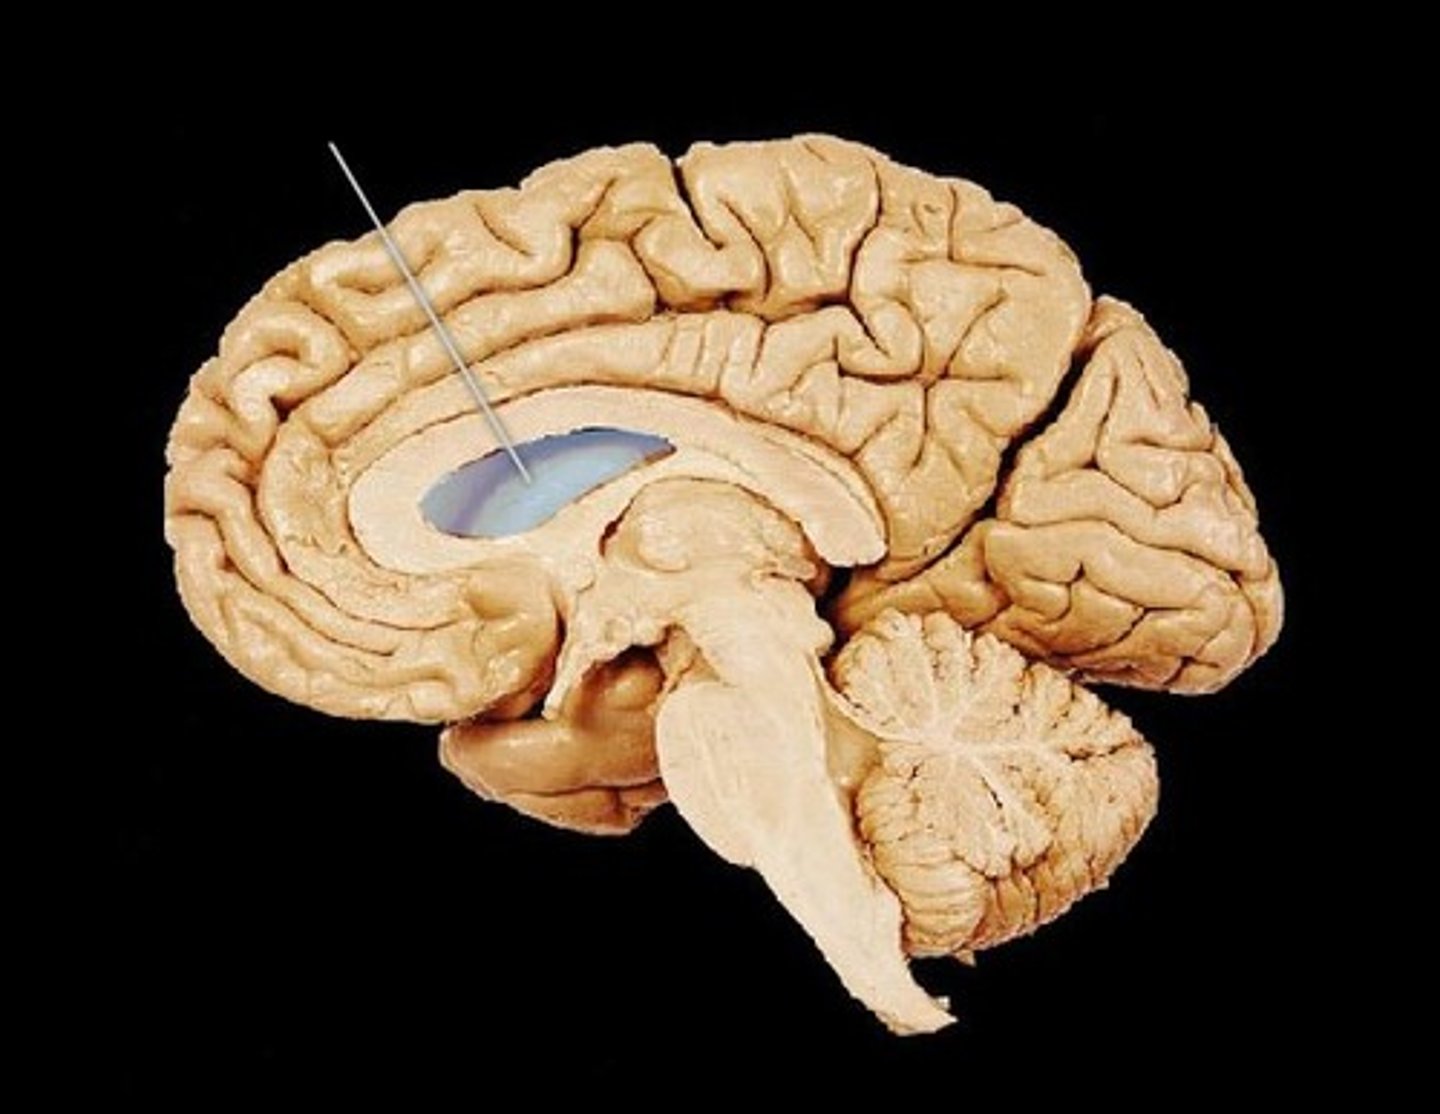

ventricles of the brain

canals in the brain that contain cerebrospinal fluid

lateral ventricles

Ventricles located in each cerebral hemisphere

third ventricle

the ventricle located in the center of the diencephalon

interventricular foramen

opening that connects the lateral ventricles and 3rd ventricle

cerebral aqueduct

connects the third and fourth ventricles

cerebral spinal fluid

made by choroid plexus